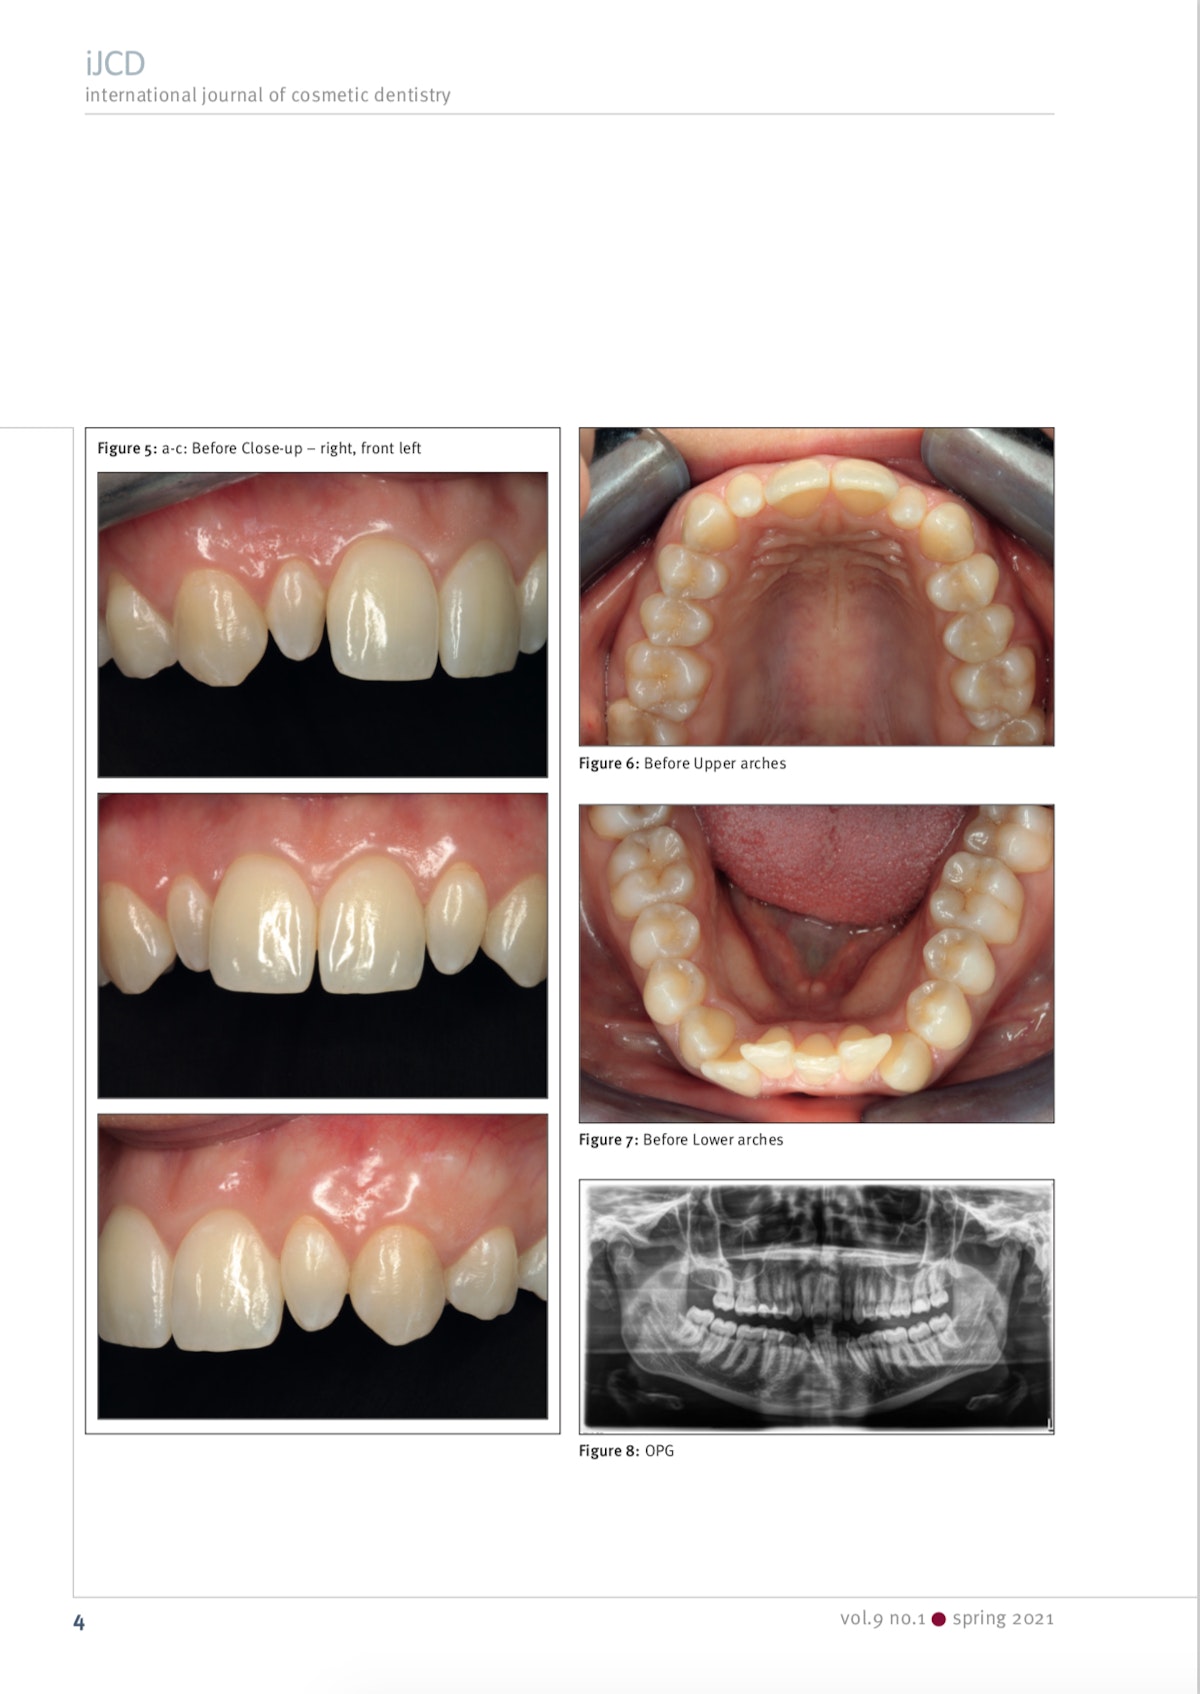

Case 1.

Alkutilanne

Hiottu hammas kuorta varten. Ikenen alla on tumma ienlanka kontrolloimassa kosteutta jäljennöstilanteessa.

Valmis kuori sementoituna.

Case 2

Ja syy sille miksi oikomista Invisalign -kalvoilla käytetään usein ennen laminaattihoitoja. Alla oleva hoito olisi ollut ehkä toteutettavissa ilman oikomistakin, mutta hampaita olisi silloin pitänyt hioa kohtuuttoman paljon. Oikomisella purentaa on parannettu, saatu purentavoimat jakautumaan hampaistossa oikein ja tätä kautta lopputuloksesta mahdollisimman pitkäkestoinen.

1. Alkutilanne ennen oikomista

2. 6kk Invisalign -hoidon jälkeen

3. Hampaat hiottuna kuoria varten

4. Keraamiset hammaslaminaatit kymmenessä ylähampaassa